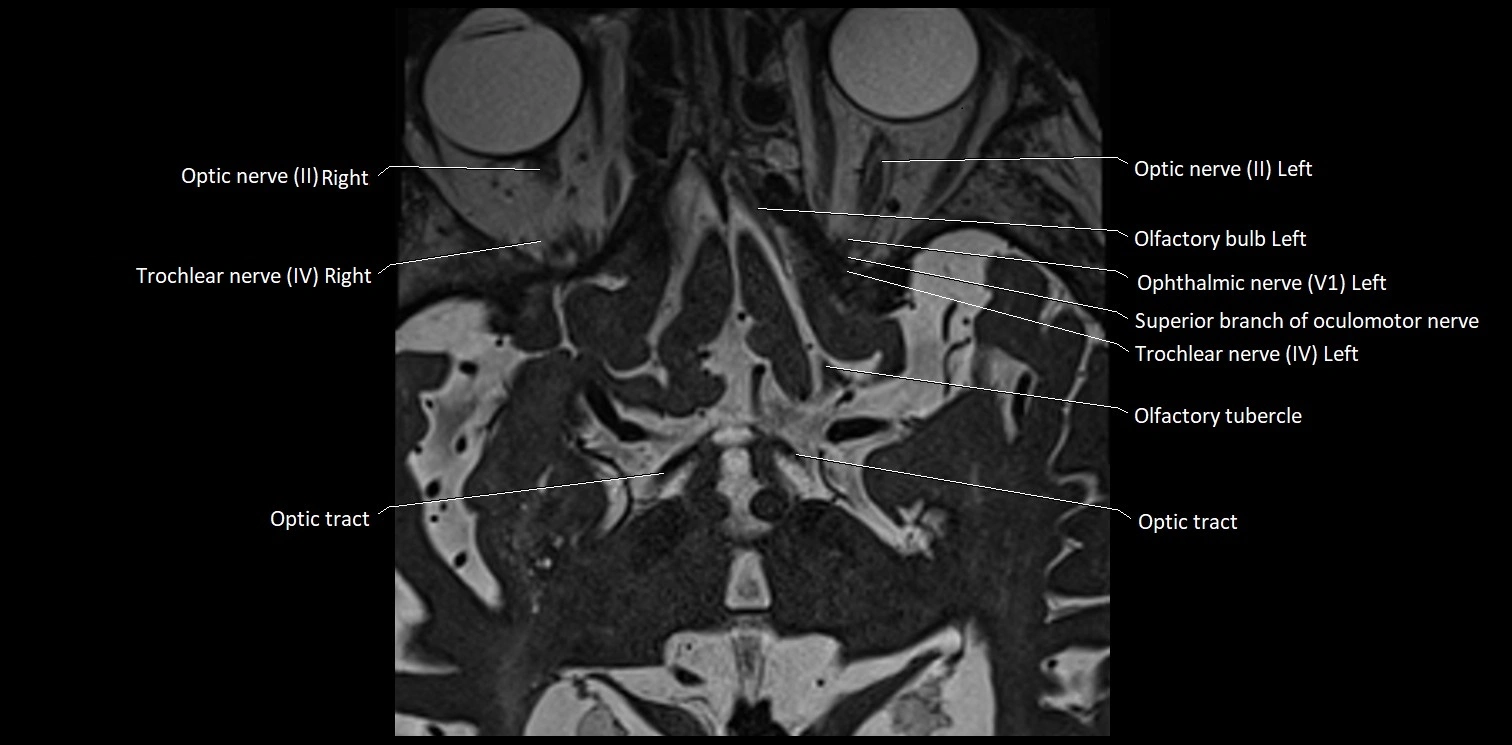

MRI Appearance

• The abducens nerve is a small, thin, linear structure

• Best visualized on high-resolution T2-weighted 3D MRI sequences (e.g., FIESTA or CISS)

• Seen as a hypointense (dark) line running from the brainstem at the pontomedullary junction, traversing the prepontine cistern, and entering Dorello’s canal under the petrosphenoidal ligament, then into the cavernous sinus, and finally the orbit

• May be challenging to visualize in standard MRI due to its small size

• Pathology may be inferred by absence, displacement, or enhancement of the nerve

MRI images

image